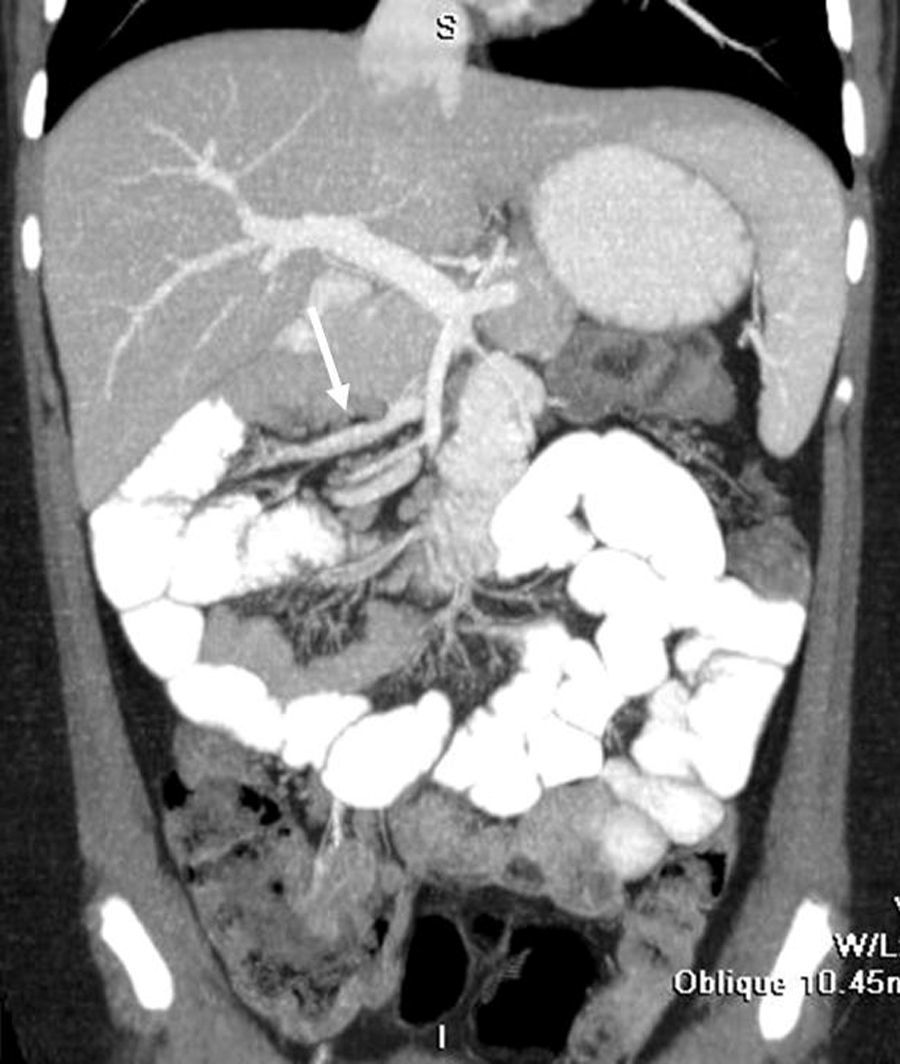

Radiología Solución del caso 52. Hernia pericecal sin obstrucción intestinal

Solución del caso 52. Hernia pericecal sin obstrucción intestinal

Solution to case 52. Pericecal hernia without intestinal obstruction